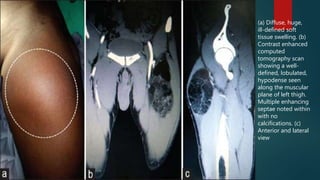

(a) Diffuse, huge,

ill-defined soft

tissue swelling. (b)

Contrast enhanced

computed

tomography scan

showing a well-

defined, lobulated,

hypodense seen

along the muscular

plane of left thigh.

Multiple enhancing

septae noted within

with no

calcifications. (c)

Anterior and lateral

view

(a) Diffuse, huge, ill-definedsoft tissue swelling. (b) Contrast enhanced computed tomography scan showing a well- defined, lobulated, hypodense seen along the muscular plane of left thigh. Multiple enhancing septae noted within with no calcifications. (c) Anterior and lateral view